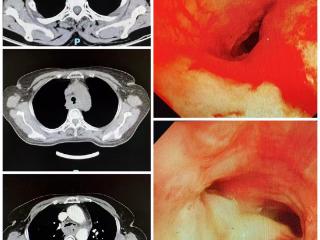

临沂市中医医院成功实施Y型支架置入术,封堵瘘口畅通呼吸